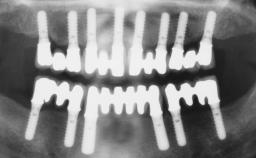

# of Implants 6

Bone Augmentation Horizontal|Simultaneous

Defining Characteristics Fully edentulous upper jaw to be rehabilitated with four or more implants

Modality 6+ implants with immediate loading

Bone Volume Horizontally and vertically sufficient